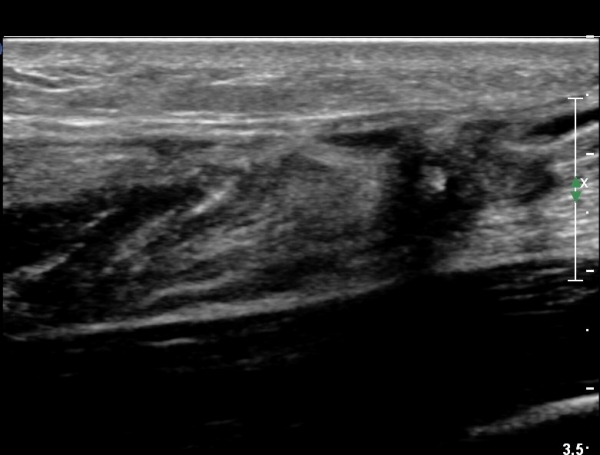

¾ÆÅ³·¹½º°Ç Á¾´Ü¸é°Ë»ç¿¡¼ ¾ÆÅ³·¹½º°Ç Àú¿¡ÄÚ ºÎÁ¾, ¿¬°á¼º ¼Ò½Ç, °ÇÁÖÀ§ ¼ö¾×Àú·ù ¼Ò°ßÀ» º¸ÀÓ(»çÁø 2, 3, 4, 5).